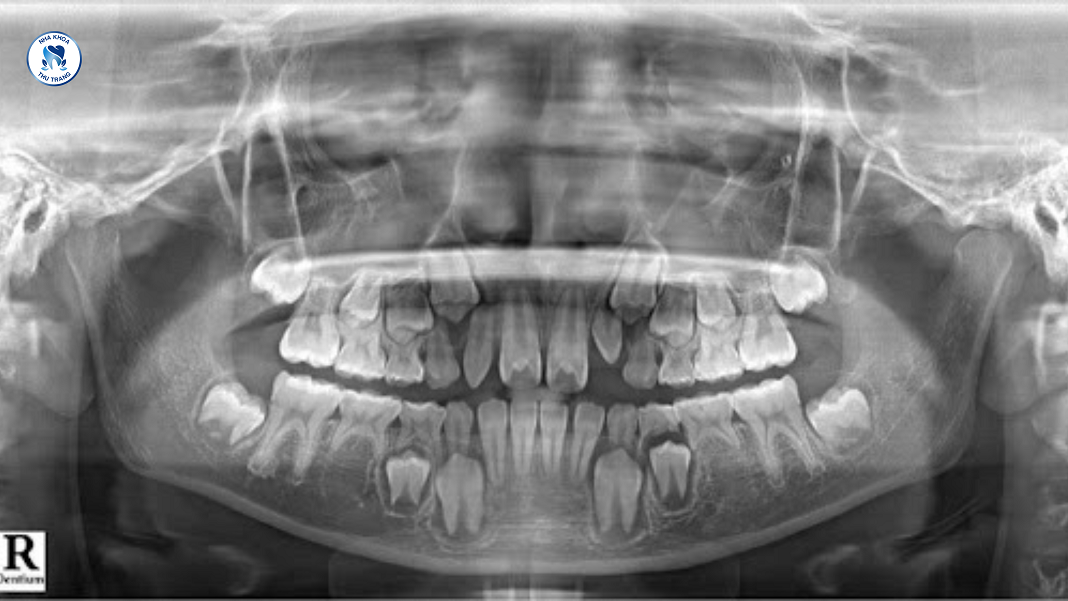

Thiếu mầm răng vĩnh viễn là gì?

Thông thường, con người sẽ có tổng cộng 32 chiếc răng. Nhưng chiếc răng này chỉ mộc lên 2 lần, khi mọc răng sữa và mọc răng vĩnh viễn. Trong đó, thiếu mầm răng vĩnh viễn là tình trạng có 1 hoặc nhiều răng trên hàm không mọc lên.

- Mầm răng có tồn tại nhưng mọc ngầm, mọc sai vị trí hoặc không có trên cung hàm.

Trường hợp có tồn tại mầm răng

Trường hợp có tồn tại mầm răng nhưng răng không mọc lên có nghĩa là răng còn nằm lại trong xương hàm. Điều cần làm lúc này là đưa chiếc răng này ra khỏi vùng nướu để răng thực hiện đúng chức năng của nó.

Để đưa răng lên khỏi nướu, bệnh nhân nên đến trực tiếp các trung tâm nha khoa uy tín. Tại đây, các bác sĩ sẽ tiến hành thủ thuật bộc lộ răng ngầm trong xương. Thông qua khí cụ được gắn vào răng, để kéo răng ra khỏi xương hàm và trở về đúng vị trí trên cung hàm.